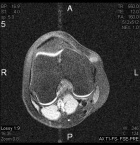

14 year old female with a tender right knee mass which has been enlarging for five months